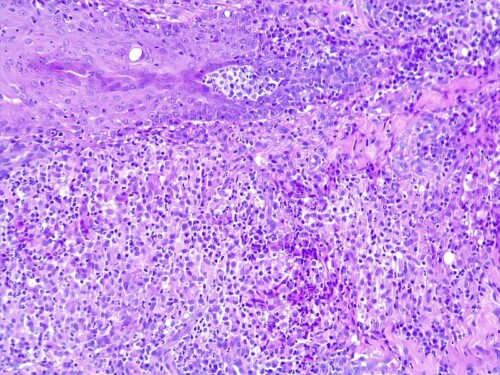

L’épiderme est atrophié, siège d’une importante hyperkératose orthokératosique, intéressant également les follicules pileux qui sont dilatés, comédoneux, avec des tiges pilaires avulsées souvent entourées d’un matériel inflammatoire mêlant granulocytes neutrophiles et des colonies bactériennes de cocci. Dans le derme, on observe au sein des unités annexielles folliculo-sébacées, une atrophie discrète des follicules pileux, des glandes sébacées et des glandes sudorales épitrichiales. Les follicules pileux sont parfois en phase télogène et catagène. La gaine conjonctive des follicules est épaissie, fibro-hyalinisée. Dans le derme, on observe de multiples foyers de métaplasie osseuse avec un derme non-inflammatoire (photos histo).

Il s’agit donc d’un cas de métaplasie osseuse cutanée (osteoma cutis) sur fond de dermatose alopéciante peu atrophiante non inflammatoire et de lésions de pyodermite associé à un syndrome de Cushing hypophysaire (maladie de Cushing).